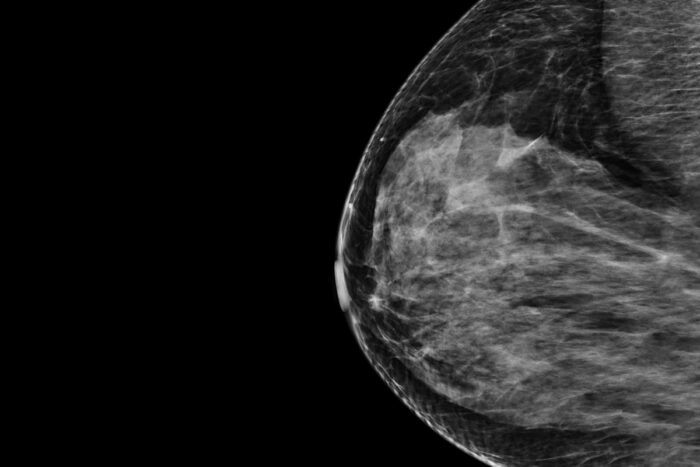

Mammography scan of a breast shown in black and whiteGetty Images

A new technology that harnesses AI to analyze mammograms and improve the accuracy of predicting a woman’s personalized five-year risk of developing breast cancer has received Breakthrough Device designation from the Food and Drug Administration (FDA). Developed by researchers at Washington University School of Medicine in St. Louis, the software has been licensed to Prognosia Inc., a WashU startup company.

The system analyzes mammograms to produce a risk score estimating the likelihood that a woman will develop breast cancer over the next five years. The technology is compatible with both types of mammogram imaging available: the four 2D views of the breast produced by full-field digital mammography and the synthetic 3D view of the breast produced by digital breast tomosynthesis. Importantly, the system produces an absolute five-year risk that makes it possible to compare a woman’s risk to an average risk based on national breast cancer incidence rates. This provides a meaningful estimate that is aligned with the U.S. national risk reduction guidelines, so that clinicians will know what steps to take next if a woman’s risk is elevated.

The software is a pre-trained machine learning system that analyzes mammogram images and provides an estimate of how likely a patient is to develop breast cancer over the next five years, based solely on images and a woman’s age. According to the developers, Prognosia Breast estimates a person’s five-year risk of developing breast cancer 2.2 times more accurately than the standard method, which is based on questionnaires that consider factors such as age, race and family history. The system was trained on past mammograms from tens of thousands of individuals who underwent breast cancer screening through Siteman Cancer Center. Some of them went on to develop cancer, teaching the system what to look for in the earliest stages of tumor development. Such early signs of disease can’t be perceived even by a well-trained human eye.